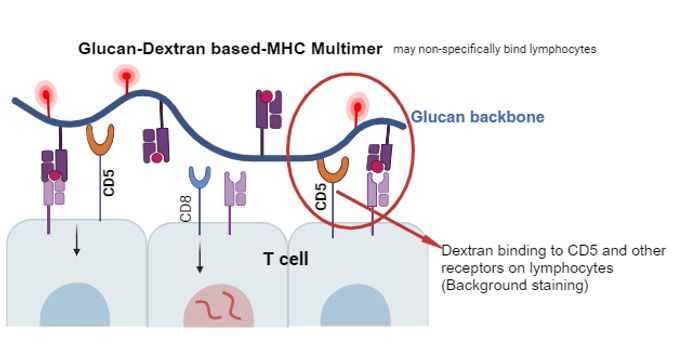

JAN 23, 2025ImmunologyThe human immune system has evolved throughout history to effectively recognize and adapt to invading pathogens. To comb ...